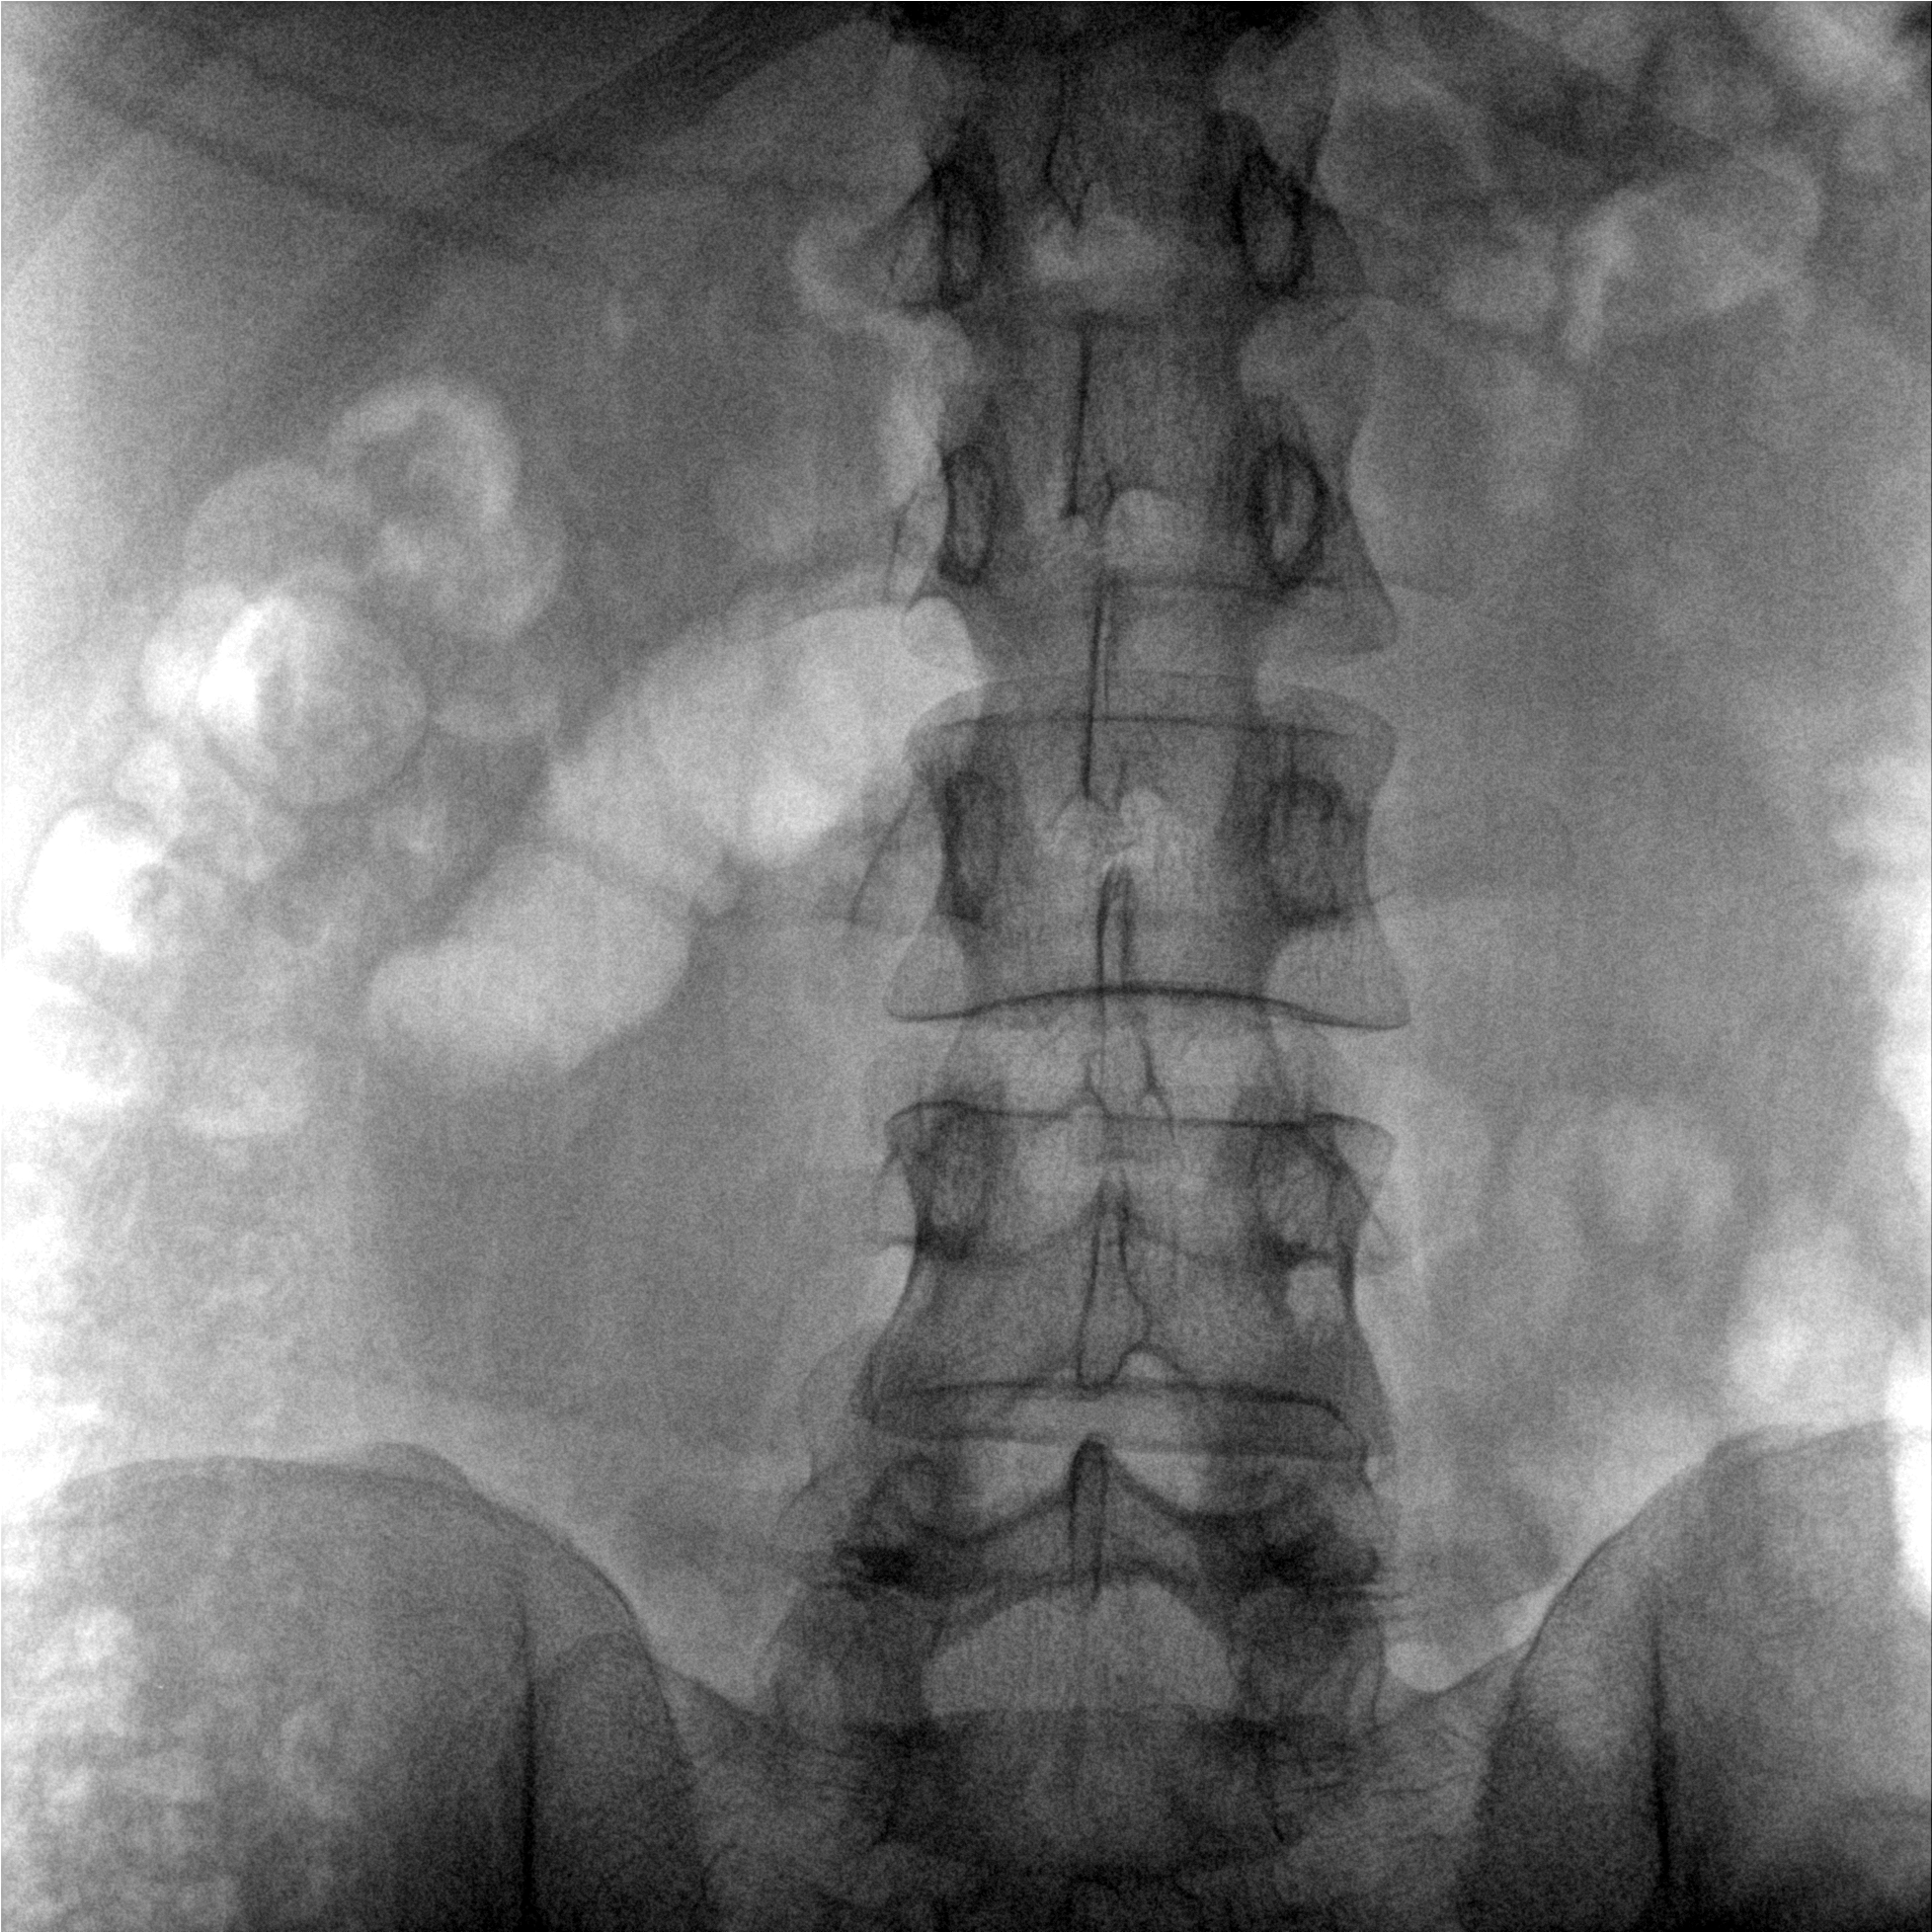

提供更大的術(shù)中三維成像視野,采集更多圖像信息,可一次拍全全段頸椎、全段腰椎、七節(jié)胸椎、雙側(cè)骶髂關(guān)節(jié)、股骨頭及單側(cè)盆骨。

在C臂掃描過程中,始終保持拍攝主體處于射線束的中心,避免了序列圖像采集過程中的橫縱方向運動,減少相對運動造成的運動偽影。